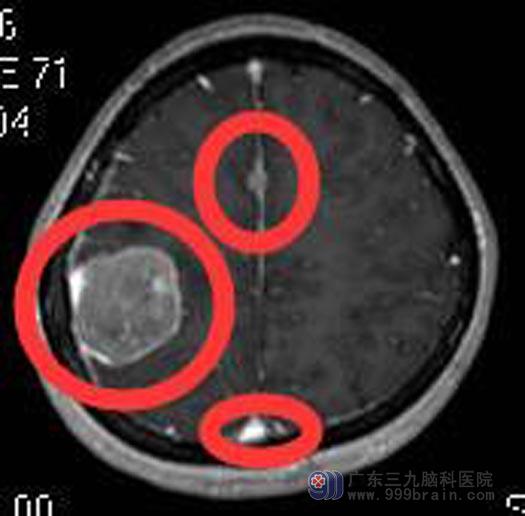

头颅MRI示:1.右侧顶部占位性病变,考虑脑膜瘤可能性大,病变大小约31mm×35mm×36mm;2.考虑纵裂池(大脑镰旁)两个细小脑膜瘤;近额部者大小约6mm×5mm×5mm,近顶部者大小约6mm×4mm×4mm。

手术前